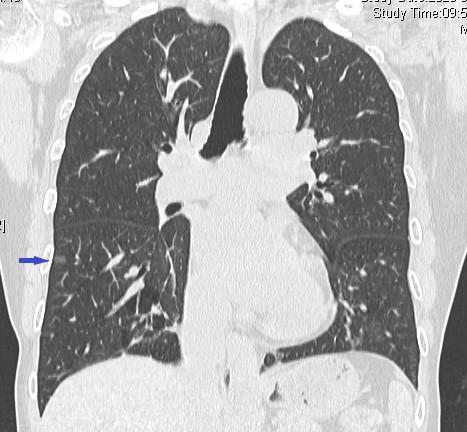

该患者胸部CT提示结节位于右肺下叶外基底段胸膜下,大小约25px,呈纯磨玻璃样改变,考虑早期肺癌可能性大,需外科切除。

为精准术前规划,在LungPro导航系统重建患者支气管、肺结节的基础上,潘小杰主任带领胸外科团队就病灶的位置、如何制定最优路线进行深入分析及讨论,充分评估病灶及染色的位置、距离等。